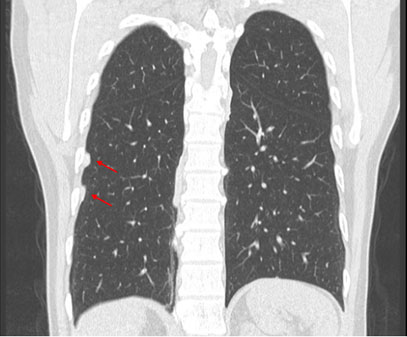

Tomografía computarizada (TC) de tórax: La TC de tórax es una técnica de imagen más precisa que puede mostrar con mayor detalle las alteraciones pleurales, como engrosamiento, calcificaciones, masas o derrame pleural (Figuras 4, 5 y 6).

Frente a la presencia de alteraciones pleurales en la Radiografía de tórax con técnica OIT y confirmadas con tomografía computarizada de tórax de alta resolución sin contraste (TCAR), será de vital importancia realizar el diagnóstico diferencial sobre alteraciones pleurales asociadas a la exposición al amianto (Figuras 2, 3, 4 y 5). Entre las patologías diferenciales se incluyen: 53

Atelectasias redondas: Es una anormalidad poco común de la pleura que se pliega sobre sí misma, atrapando el tejido pulmonar adyacente y dando lugar a la formación de una imagen curva en los bronquios y vasos sanguíneos que se dirigen hacia esa zona, lo que se conoce radiológicamente como "cola de cometa". 61 Aunque teóricamente puede verse en la fibrosis pleural de cualquier origen, en la práctica la mayoría de los casos están asociados a la exposición a fibras de amianto. En la tomografía axial computarizada de tórax, se identifica por tres signos radiológicos característicos: una masa redonda u ovalada de 2.5 a 7 cm que contacta la superficie pleural, la presencia de una estructura lineal en forma de cola en su interior correspondiente a los elementos broncovasculares y el engrosamiento de la pleura subyacente. 62 Es importante distinguir una atelectasia redonda de un carcinoma broncogénico, ya que su apariencia en la imagen puede ser similar.